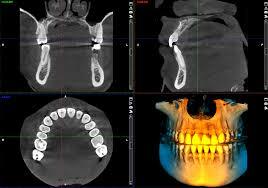

В современном стоматологическом мире точная диагностика играет ключевую роль в успешном лечении пациентов. Одним из самых передовых инструментов для достижения этой цели является дентальный томограф, он позволяет получать трехмерные изображения зубочелюстной системы, что значительно улучшает качество диагностики и планирования лечения.

Наш томограф поддерживает различные режимы сканирования, включая 3D-томографию и панорамные снимки, что делает его идеальным решением для широкого спектра стоматологических задач — от имплантации до ортодонтии.

Дентальный томограф Planmeca ProMax 3D Classic находит свое применение в различных областях стоматологии:

• Имплантология: Точные 3D-изображения помогают в планировании установки имплантатов, учитывая анатомические особенности пациента.

• Ортодонтия: Стоматологи могут более точно оценивать положение зубов и челюстей, что улучшает результаты лечения.

• Хирургия: Снимки помогают хирургу лучше подготовиться к операциям, минимизируя риски и повышая безопасность процедур.

• Терапия: лечение корневых каналов зубов с применеием томографа проходит с максимальной точностью